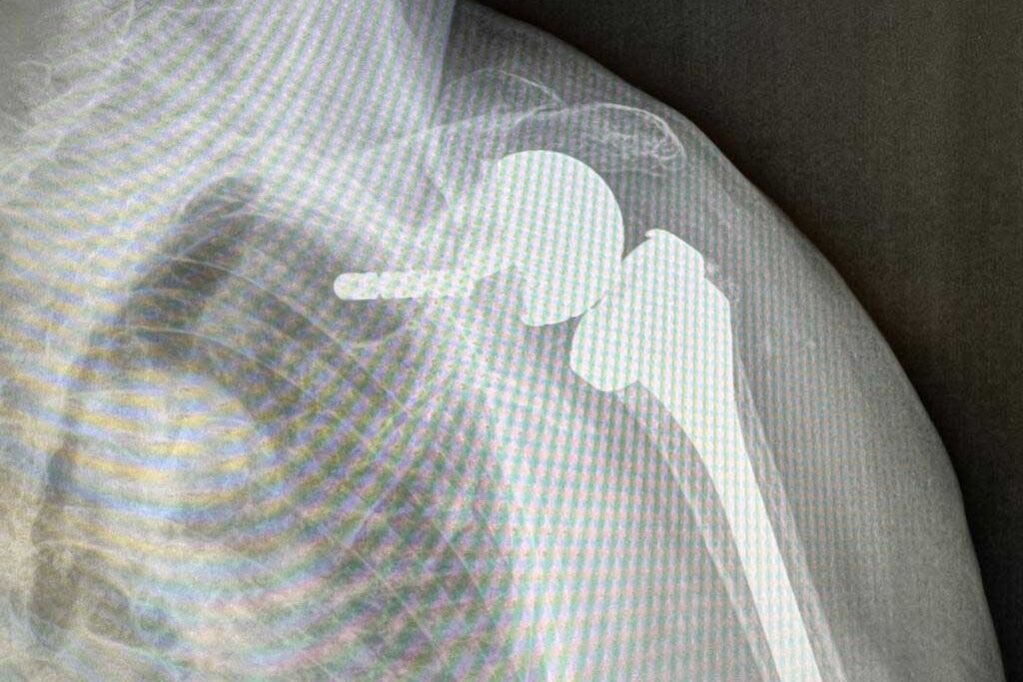

Questo tipo di intervento coinvolge la rimozione della testa dell’omero (osso del braccio superiore) e la sostituzione con una protesi inversa, che inverte il ruolo delle componenti ossee dell’articolazione.

Durante l’intervento chirurgico, il chirurgo rimuove la testa dell’omero danneggiata e inserisce una componente protesica sferica nell’omero.

L’impiego di una protesi inversa significa che la sfera viene fissata sulla glena, che è una parte della scapola (osso della spalla), mentre la cavità articolare viene posizionata sull’omero.

Questa inversione dei ruoli permette di ottenere una maggiore stabilità e un migliore funzionamento dell’articolazione.

Alle volte il paziente arriva con la spalla troppo deformata per cui bisogna, in questi casi, applicare questo tipo di protesi che fa lavorare semplicemente il deltoide ed esclude dall’azione biomeccanica gli altri tendini ormai logorati.